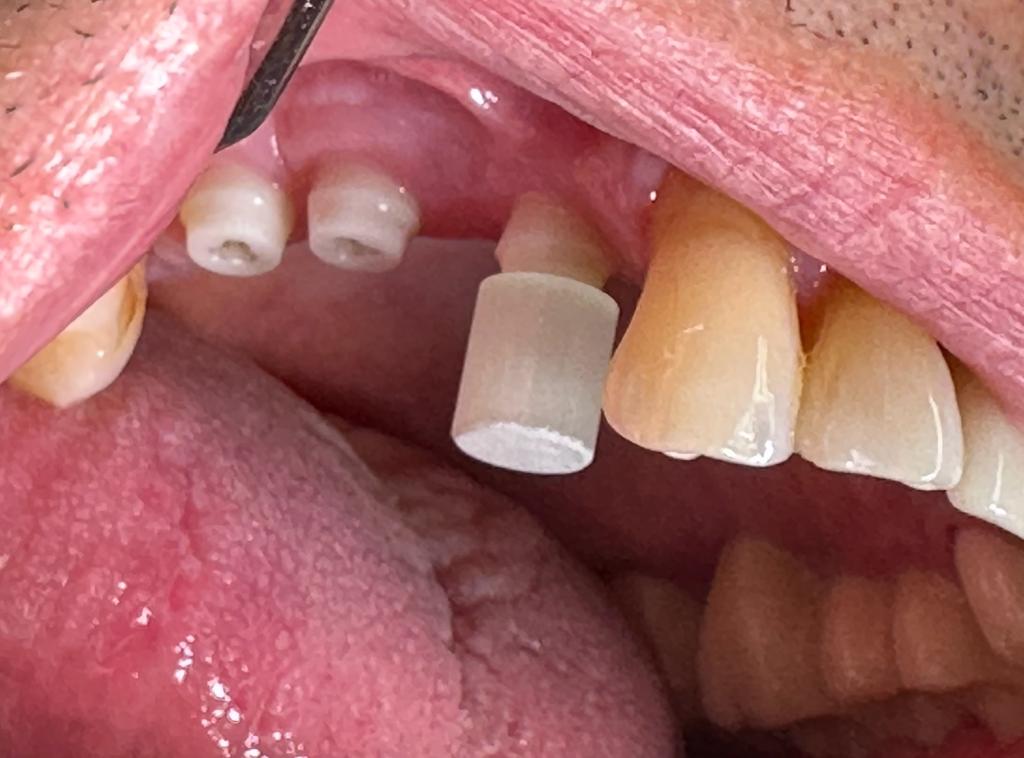

Le esigenze estetiche dei pazienti aumentano con l’accettazione e la diffusione dell’implantologia, che tra l’ampia cerchia di popolazione viene considerata come la migliore soluzione all’edentulia. In questo ambito l’impianto in zirconio whiteSKY permette di offrire, a pazienti esigenti,pazienti con allergie ai metalli e in particolar modo al titanio,soluzione d’elevata qualità e sopratutto estetiche. Nessuna ombra scura precluderà l’aspetto estetico, persino con gengive estremamente sottili. WhiteSKY si propone anche come soluzione per pazienti sensibili ai metalli, poichè lo zirconio non ha proprietà metalliche. Da studi condotti emerge che il deposito di placca è notevolmente inferiore, ripetto a quello sulle superfici in titanio, alle stesse condizioni capacità di osteointegrarsi sovrapponibile all’impianto in titanio. Il pericolo di periimplantiti si riduce notevolmente, grazie alla minima quantità di germi patogeni presenti nel biofilm. I risultati clinici con gli impiant in zirconio confermano le aspettative di un successo a lungo termine, che vengono comprovate dalla ricerca scientifica. WhiteSKY è un impianto monofasico, e pertanto è necessario porre particolare attenzione alla fase di osteointegrazione. Per la sua monofasicità, è assolutamente necessario prestare particolare attenzione alla pianificazione prechirurgica. Subito dopo l’inserimento, l’impianto in zirconio puo’ essere preparato e individualizzato. Dopo aver preso l’impronta, viene posizionata la protesi fissa provvisoria che il paziente porterà x alcuni mesi, il manufatto definitivosarà in zirconio stratificato o pieno a secondo dell’estetica della zona impiantata.

L’impianto Ceralog Hexalobe è invece bifasico,consente l’utilizzo di soluzioni protesiche avvitabili e di conseguenza reversibili,Gli abutment sono in PEEK,è un materiale molto duttile che in condizione di carico si comporta in maniera ottimale.E’ un materiale radiotrasparente.